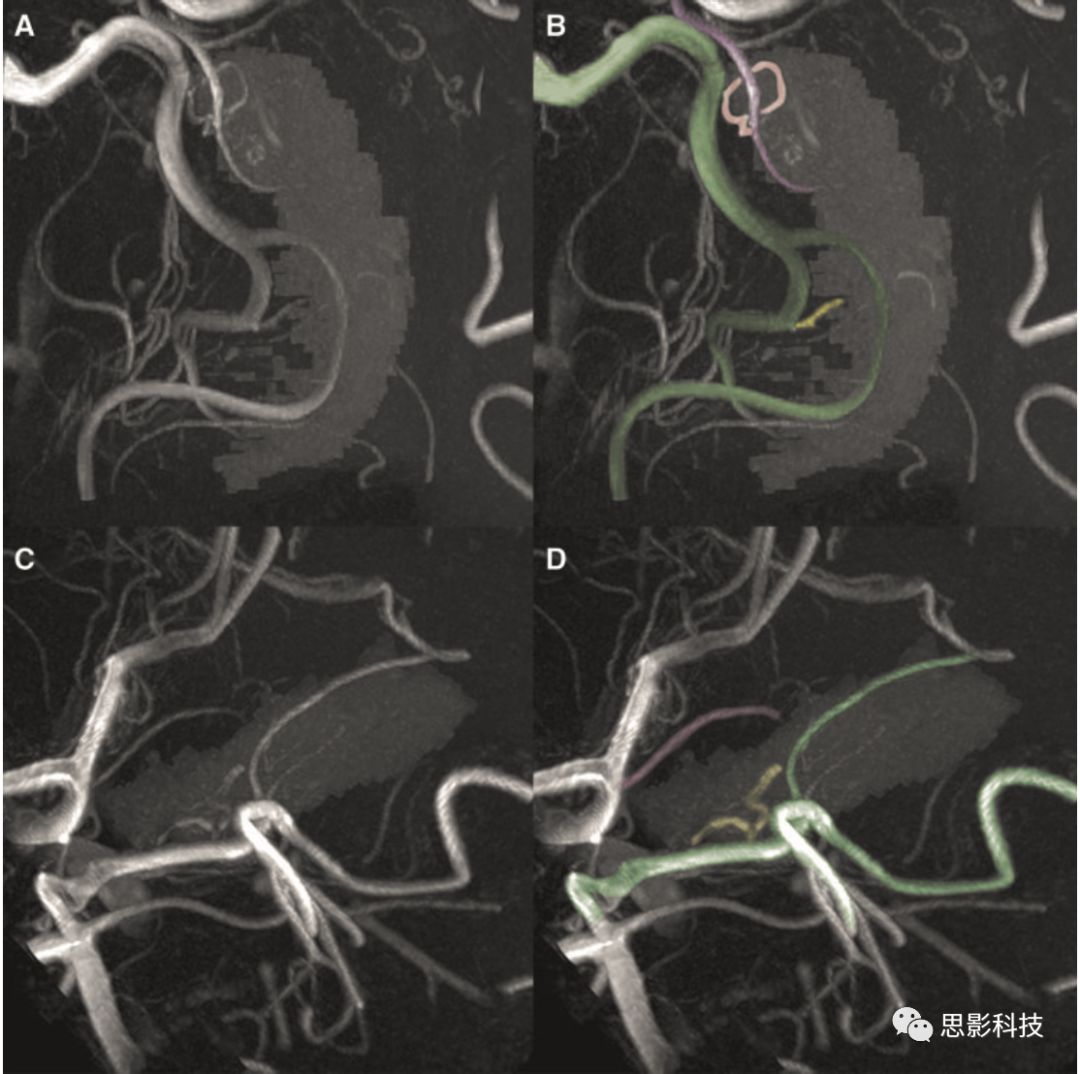

首先通過MRIcron軟件包內(nèi)的dcm2nii7T T1以及TOF DICOM格式數(shù)據(jù)轉(zhuǎn)為NIFTI格式。然后T1圖像在SPM12內(nèi)進行處理。為確定海馬血管模式,首先需要制定每個被試的海馬mask。本研究通過FreeSurfer 6.0進行自動分割,提取雙側(cè)海馬并獲得其體積,同時也獲得顱內(nèi)總體積。接下來,海馬mask以及T1均配準(zhǔn)到TOF上(使用Advanced Normalization Tools,ANTs)。為了清楚辨認海馬血管供應(yīng)模式,利用MeVisLabTOF成像進行處理達到最大強度投影。如果觀察到脈絡(luò)膜前動脈末端分支穿過海馬區(qū)域,則判定為海馬混合血管供應(yīng)模式。因為同一個體雙側(cè)海馬血管也存在變異,所以研究者利用海馬血供評分進行分組,Group 0表示雙側(cè)海馬均為單血管供應(yīng)模式,Group 1表示至少一側(cè)為海馬混合血管供應(yīng)模式(圖1)。本研究共47例被試,所以探討了94個海馬,其中只有85個海馬可以識別其血管模式。剩下來的9個海馬血供模式存在疑問,可能由于偽差或者吻合口小血管混淆。

1AB圖為海馬混合血管供應(yīng)模式。

圖中綠色的血管代表大腦后動脈,黃色血管為其供應(yīng)海馬的分支,紫色血管為脈絡(luò)膜前動脈,粉色血管為其發(fā)出的分支,可以明顯看到大腦后動脈與脈絡(luò)膜前動脈均為海馬供血。而CD圖為海馬單血管供應(yīng)模式,僅有大腦后動脈分支進行供血,未見脈絡(luò)膜前動脈發(fā)出分支供血。